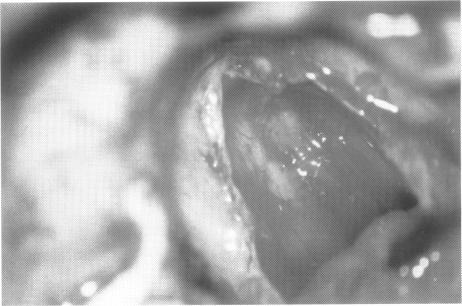

Surgery of acoustic neuroma (AN) has significantly refined over the past years due to a series of advances in diagnostics and surgical technique. Electrophysiologic investigation performed during surgery has greatly contributed to this progress, increasing the surgeon's understanding of the mechanism of damage and suggesting various changes in his or her surgical strategy.In this context, the advantages of the retrosigmoid "en-bloc" removal of small to medium size ANs have been examined in the present study. At the ENT Department of the University of Verona, 103 subjects with AN were operated on, from January 1990 to December 1995, with a retrosigmoid-transmeatal approach. Eighteen subjects (17.4%) presented pure a intracanalar (IC) tumor and 85 (82.6%) had both IC and extracanalar (EC) involvement. All the IC tumors (n = 18) and 70 of the IC-EC neuromas with an EC size less than 25 mm are reported in this paper for a total of 88 patients. The first 48 patients were operated on via the classic procedures described in the literature, characterized by removal of the tumor after "debulking" and limited exposure of the internal auditory canal (IAC). The following 40 subjects were operated on according to the technique of "en-bloc" removal of the tumor and wide exposure of the IAC.In the "en-bloc" group the tumor was first detached from the cerebellar flocculus and the pons, when necessary. The tumor was not debulked to preserve the anatomic relationship with the nerves and to facilitate identification, cleavage and dissection of the tumor from the neural structures. Thereafter, the posterior wall of the IAC was drilled out and opened in a circumferential range from 180 to 270 degrees . The IAC dura was subsequently opened, and the distal end of the AN along with the vestibular nerves were identified. The vestibular nerves were sectioned in the distal portion of the IAC and dissected with the tumor from the underlying facial and cochlear nerves. Dissection continued medially to the IAC porus. The AN was progressively dissected from the cochlear and facial nerves in the cerebellopontine angle (CPA) with multiple direction maneuvers, as required by the characteristics and degree of adherence to the neural structures.The anatomic and functional results obtained with this new procedure ("en-bloc" removal) were compared with the classic "debulking" technique. The statistical analysis shows an improvement in postoperative outcome for both auditory and facial nerve function. The "en-bloc" removal procedure along with the wide exposure of the content of the IAC and electrophysiologic monitoring of the seventh and eighth cranial nerves are, in our experience, the recommended strategies for improving outcomes in small to medium size ANs.